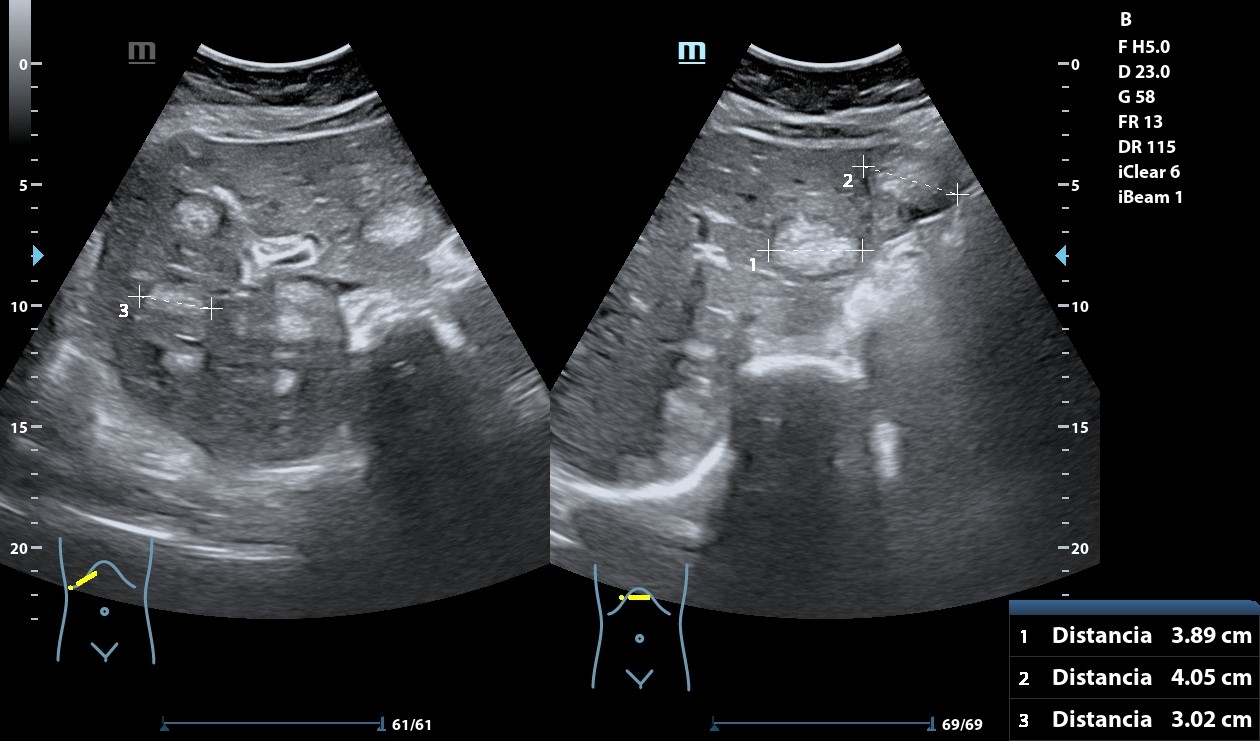

Hígado con abundantes LoEs hiperecogénicas con halo hipoecogénico. Retroperitoneo con abundantes imágenes redondeadas, hipoecogénicas peripancreáticas y retroperitoneales que llegan a medir 28 mm. A nivel de fosa ilíaca izquierda se observa imagen en pseudoriñón que con Doppler presenta captación y llega a medir hasta 72,2 mm.